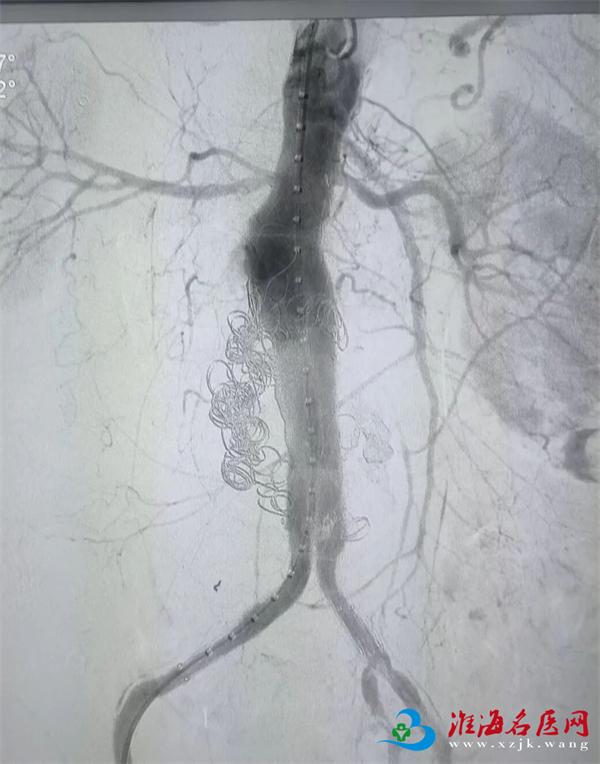

晚8点14分,手术开始。术中,杨继武带领团队通过股动脉穿刺建立通道,将覆膜支架精准输送至动脉瘤破裂部位,释放后成功隔绝破损血管,牢牢“堵住”出血点,随着监护仪上血压平稳回升,晚10点55分,手术顺利结束,袁先生腹腔出血已成功控制。术后患者即刻转入ICU,医护团队通过动态调整药物精准调控血压,严密监测生命体征与病情变化,严防并发症。术后第3天,袁先生平稳转出ICU并能下床活动,目前已顺利出院。

左:术前;

右:术后